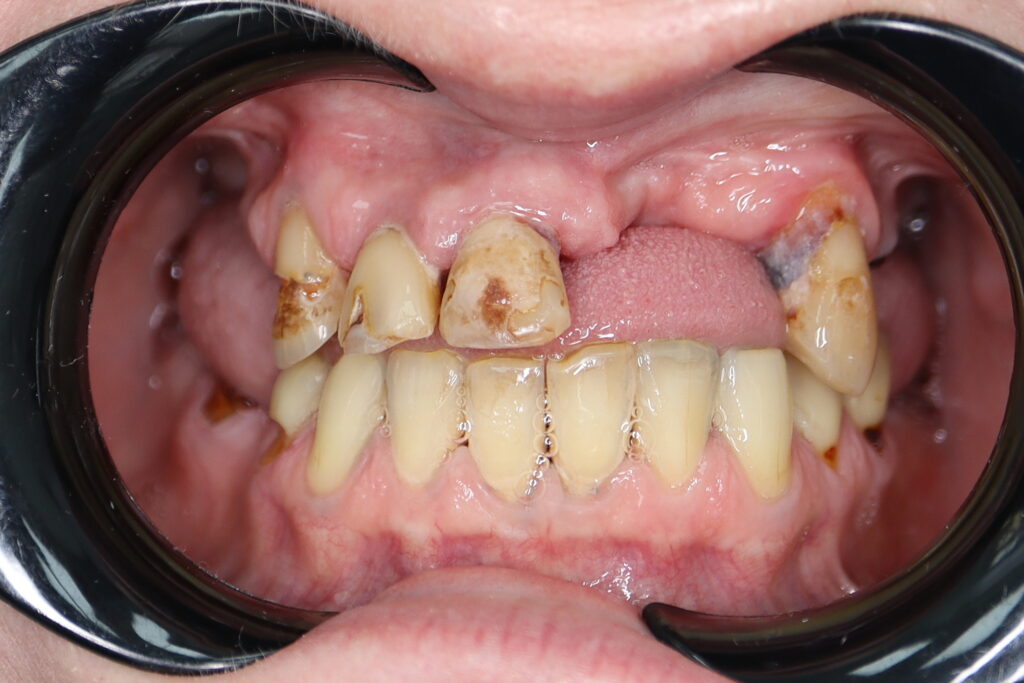

Ситуация до лечения

Жалобы: Пациент обратился с целью тотальной имплантации верхней челюсти.

Диагноз: Частичная вторичная адентия верхней челюсти.

пациент до тотальной имплантации